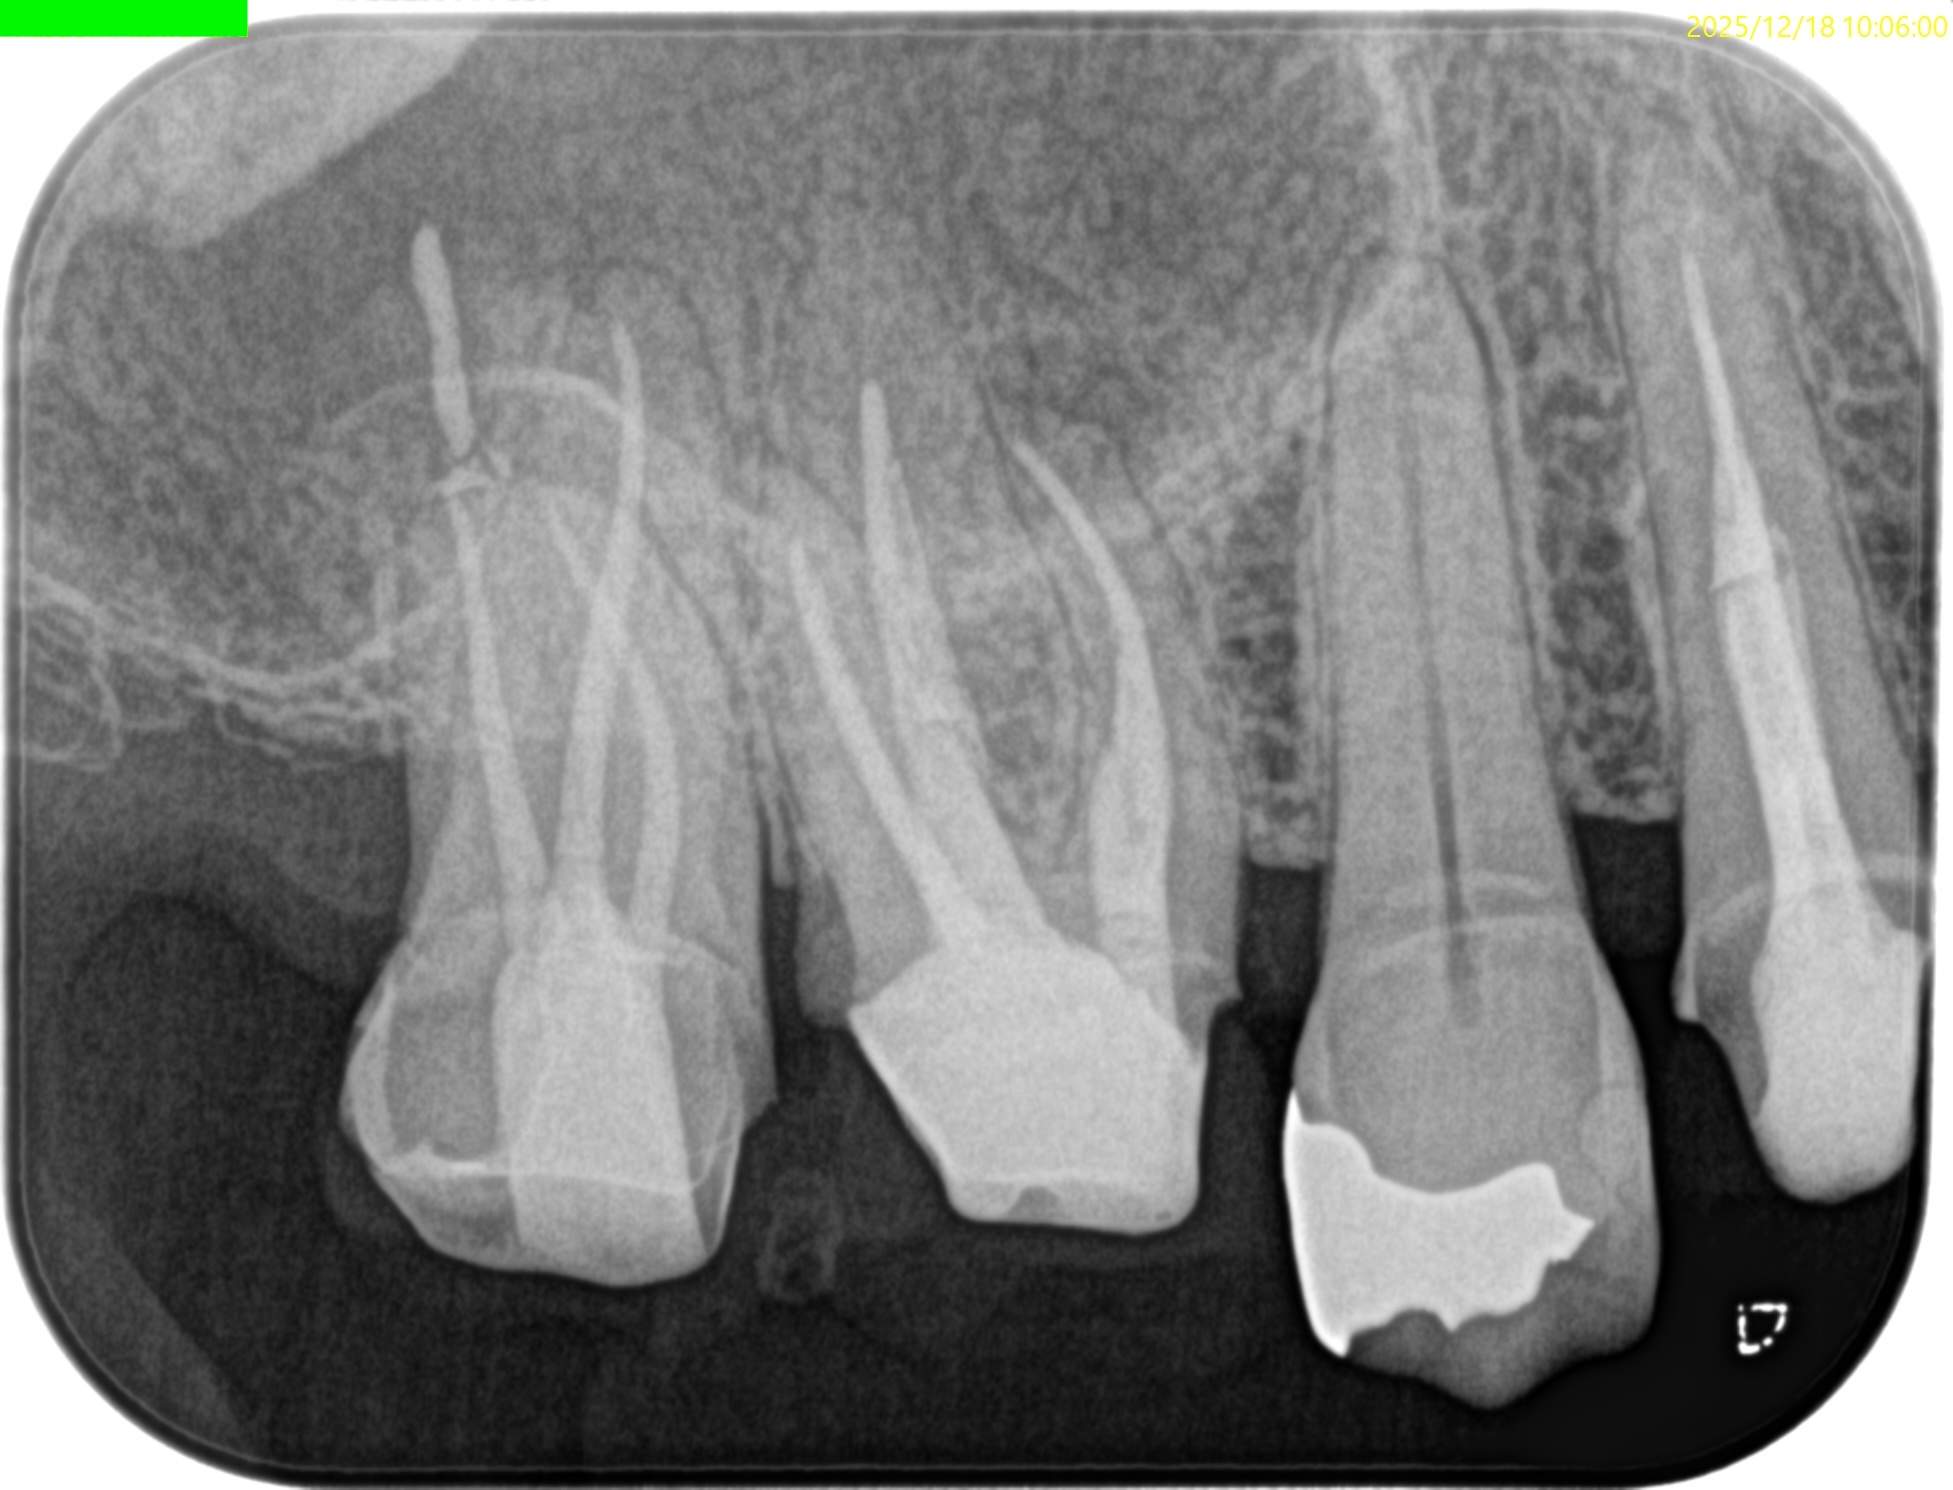

紹介患者さんの治療で、#3 MB Apicoectomyを行ったのだが

MBをRoot resectionした。

ここまでは容易なのだが、この後に逆根管形成・逆根管充填を行うが、

明後日の方向に逆根管形成・逆根管充填してしまう

それだけならばいいのだが、

この状態ではMB2の封鎖がままならない。

つまり、やり直しが必要だ。

その際は、この穿孔部を消去したいので

さらに切断部位から4mm, 頬舌的幅径が6.7mm必要だが再切断し逆根管形成・充填を試みることにした。